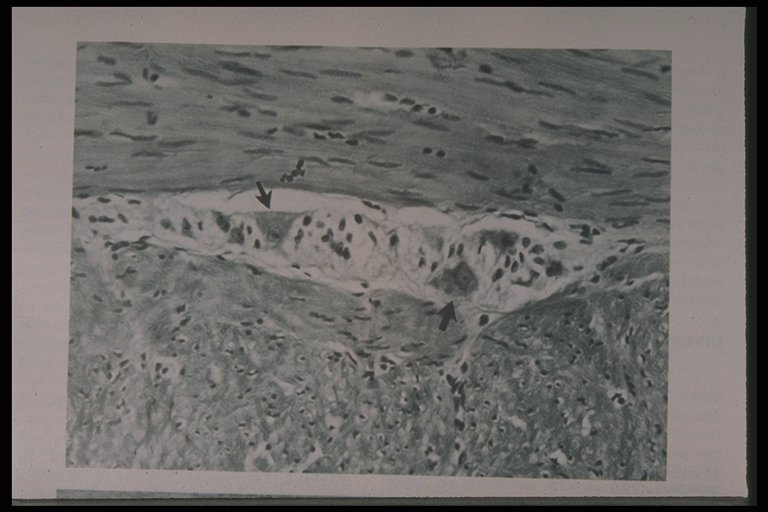

Ganglion cells (arrow) are demonstrated in normal bowel segment